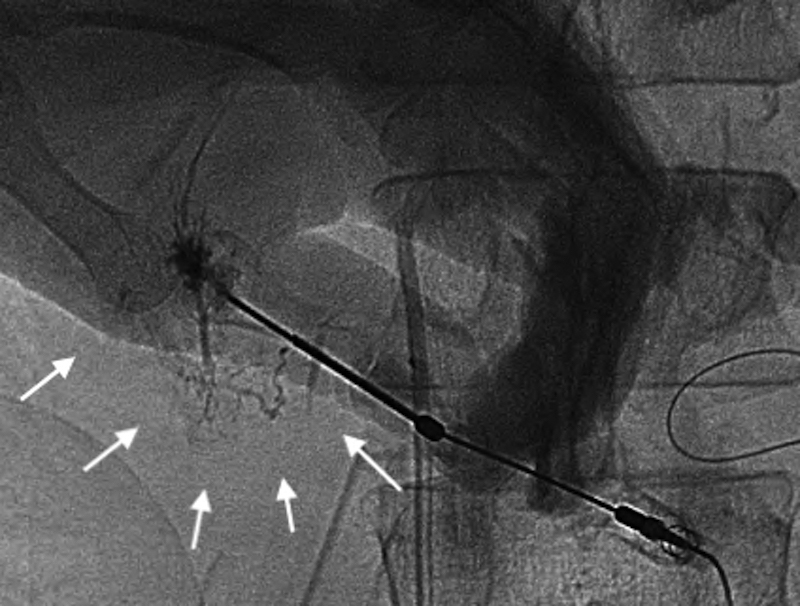

再手術後経過:再手術後はICUに収容し,高度なCOPDを合併していることから人工呼吸器による呼吸管理を行った.また,低タンパク血症に対してアルブミン製剤の投与と利尿剤の投与を行い膠質浸透圧を維持することに務めた.しかし,初回手術28日目に血圧が80 mmHg台に低下し,大量輸液,昇圧剤(ドーパミン製剤,カテコラミン製剤)の投与を行ったが反応に乏しく,同日の尿量は330 mlと乏尿となりpreshock状態と判断した.初回手術29日目にはWinslow孔に挿入していたドレーンからの排液が1,500 mlと増加したため,そのアルブミン濃度を測定すると1.9 g/dl(同日の血清アルブミン値,2.2 g/dl)と高い値を示し,一方トリグリセリドは31 mg/dlと低値であった.以上より,ドレーンの排液は腹水ではなくリンパ漏であり,食事摂取中に全く白濁を認めなかったため乳糜を含む腸管由来のリンパ液ではなく,また大動脈周囲に手術操作が及んでいないため腸骨大動脈リンパ漏は考えにくく,障害肝からの肝リンパ漏の可能性が高いと考えた.そこで,初回手術30日目よりリンパ漏に対する対処としてオクトレオチド酢酸塩300 μg/日の持続皮下注射およびエチレフリン塩酸塩120 mg/日の持続静脈内投与を開始した.同日午後より,大量輸液とアルブミン製剤の積極的な投与がリンパ漏出による循環血漿量の減少に追いつき始めたため血圧は100 mmHg以上となり,尿量も1,000 ml以上確保された.しかし,以後もドレーンの排液は減少せず,初回手術34日目には再手術後経過中最も多い1日1,530 mlに達した.このため,このまま保存的な対処では再びショック状態に陥る危険があると判断し,初回手術36日目に直接肝臓のリンパ管を塞栓する目的でPTLを施行した.エコーガイド下に21 GのPTC針を前区域グリソンに穿刺し,透視下に造影剤イオパミドールを少しづつ注入しながら引き抜くと門脈,胆管が造影された後に肝リンパ管が造影されたため,約5 mlを急速注入した.さらに,リピオドールも続けて注入したが,呼吸性変動により針先が動き,多くは門脈と胆管に流れたが一部はリンパ管内に入ったため手技を終了した.イオパミドール注入後の画像を確認するとリンパ液漏出部位は判然としなかったが,肝前区域から肝門に至るリンパ管が網目状に造影されており,リンパ管の内膜の炎症じゃっ起には有効な手技ができたものと判断した(Fig. 2).また,その後のリピオドール注入後の画像では一部は肝門部から肝十二指腸間膜にかけてのリンパ管にリピオドールがまだらに残存しており,リンパ管の塞栓もなされたものと考えられた(Fig. 3).PTL翌日に撮影した単純CTにて肝十二指腸間膜内にリピオドールの貯留した蛇行するリンパ管が確認された(Fig. 4).PTL施行翌日の初回手術37日目以降はドレーンからの排液量はほぼ半減し,500~600 ml程度となりvital signも安定した.しかし,数日経過を見てもそれ以上の減少傾向を認めなかったため,初回手術42日目,44日目,47日目にWinslow孔ドレーンよりOK-432 10 KEを生理食塩水10 mlに溶かして注入し120分間クランプし,その後解放するという処置を行った.初回手術48日目から,それまでサラサラの無色透明なドレーン排液だったものにフィブリンが混じるようになり,初回手術49日目にドレーン排液が完全にゼロになった.ドレーンが閉塞したためと考えられ,その後軽度な腹部膨満が生じ,エコーで確認するとモリソン窩に液体貯留を認めたが徐々に軽快し,初回手術62日目にドレーンを抜去した.また,アルブミン製剤の投与は初回手術60日目に終了した.初回手術78日目から経口摂取を再開したが腹部膨満は認めず,以後はほぼ順調に経過し,呼吸器リハビリテーションに時間を要したが初回手術152日目に自宅に退院した.手術後の臨床経過をFig. 5に示した.

PTL shows a fine and tortuous network of intra-hepatic lymphatics toward the hepatic hilum (arrows).